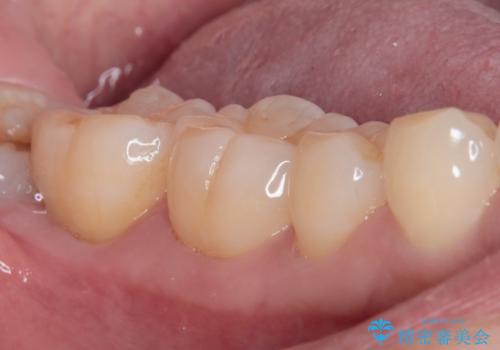

処置後神経の反応が正常であることを確認して、オールセラミッククラウンを装着しました。